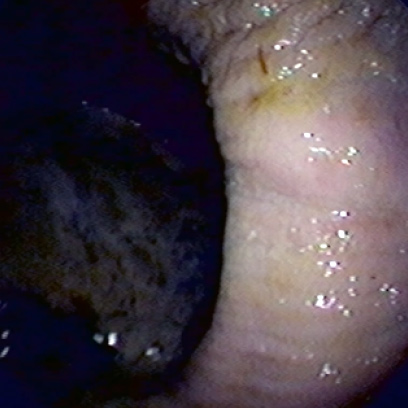

¿CUÁNDO DERIVA EN

ÚLCERA GÁSTRICA?

Cuando la irritación e inflamación gástrica en equinos progresa, la mucosa del estómago se erosiona y puede desarrollar una úlcera gástrica o lesión ulcerativa.